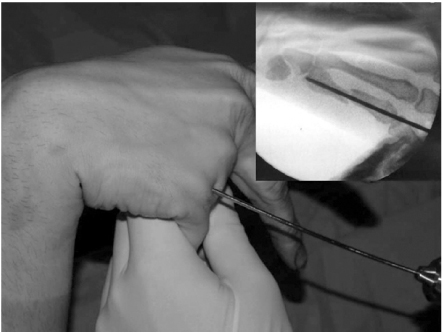

Fig. 1

1.6 mm K-wire is inserted from metacarpal head with metacarpophalangeal joint flexion for easy access to the medullary canal.

Fig. 2

When the wire tip passes fracture site and reaches to metacarpal base, wrist is bent maximum and further penetration is performed to proximal area.

The surgery was performed under general or regional anesthesia with image intensification, preferably with a tourniquet on the upper arm. Under the fluoroscopy, closed reduction of the metacarpal fracture was achieved by manipulation, and 1.6 mm K-wire was inserted from metacarpal head with MP joint flexion for easy access to the medullary canal (Fig. 1). When the wire tip passed fracture site and reach to metacarpal base, wrist was bent maximum and further penetration was performed to proximal area (Fig. 2). The distal end of K-wire was pulled up until its tip end lay within the metacarpal head (Fig. 3). Penetrated proximal part of wire was bent over, cut and buried under the skin (Fig. 4). During this procedure, any rotation of fracture was carefully checked with passive flexion and extension motion of the finger. Ulnar gutter splint was applied for rotational stability and pain relief. It was changed to extension block splint and encouraged motion exercise from postoperatively 1 week. After fracture healing, the wire was removed with local anesthesia in the outpatient department in all cases. We make small skin incision at proximal bended wire and pull out that with local anesthesia.